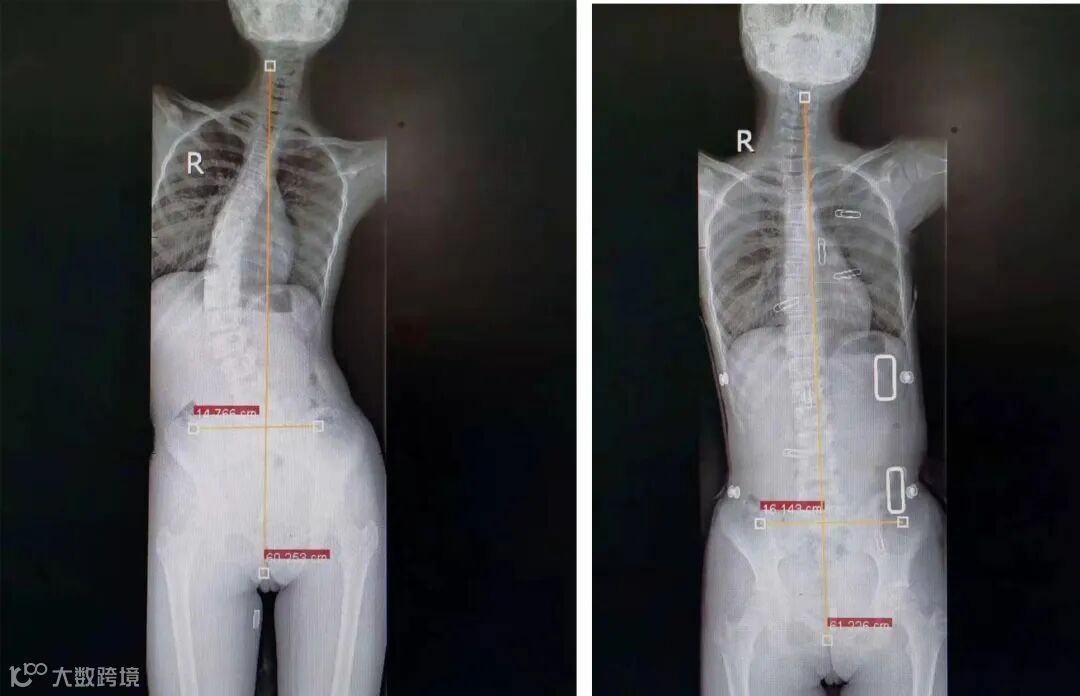

支具矫正前后DR片对比

今年4月中旬,16岁的高二女生小黄在姐姐陪同回到医院检查,经过两年多的矫正治疗,脱下支具复查DR片,效果明显,脊柱侧弯矫正基本回归中线变直,脊柱侧弯从原来的45度纠正到8度,脊椎侧弯控制可在最接近中线的位置上,直至成长发育到骨头发育成熟。而且小黄以前腰背疼痛等不舒服的症状几乎没有了,也不影响学习。

2018年12月家人发现该生背部突起,高低不平,前来市人民医院康复科就诊,拍片结果让大家都倒吸一口气,原本笔直的脊柱却呈现为C型,脊柱以T7为中心向左侧弯45度。

罗斌为其定制第一个支具及康复训练,矫正效果明显,脊柱侧弯矫正回归中线变直,脊柱侧弯8度。该女生还需要坚持定期康复训练和复查,三到六个月回院复诊一次,治疗到18-20岁才能稳定。